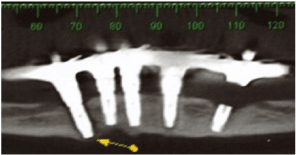

During the visit, an increase in volume was observed in the posterior region of the mandible on the right side and mobility in the region of the most distal implant, where it was impossible to diagnose whether the mobility was from the implant or resulting from the mandibular fracture (Figure 1). After the images were examined, a radiolucent line was observed beginning at the crest of the flap and continuing to the basal at the implant, characterizing a mandibular fracture without detachment of fragments. It was also possible to observe that this was a mandible with little bone height and the other implants revealed marginal bone loss with the exception of one (Figures 2 and 3).

Figure 2: Tomographic cuts where the fractured implant can be observed on the left side of the mandible and the radiolucent peri-implant of the distal implant on the right side, suggesting mandibular fracture.